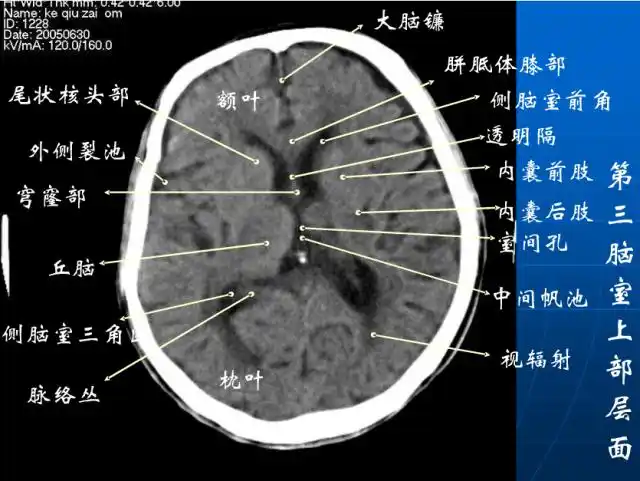

颅脑ct解剖口诀及彩色解剖图

头颅ct 解剖图谱,人手一份

头颅ct解剖与常见出血梗死判读

读懂头颅ct并不难教你成为读片小能手

详细标注版——颅脑ct正常解剖图谱_中央_小脑_纤维